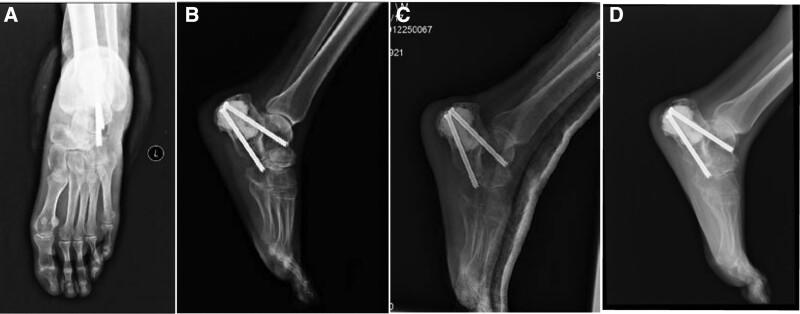

The patient underwent total calcanectomy, inactivation of calcaneus tumor, and reconstruction with cement. The Achilles tendon was detached through a Cincinnati incision. No adverse events occurred both during and after the surgery. At the last follow-up of 29 months, the patient claimed no pain, no evident limp, or any limitation of daily activities. Image examination, weight-bearing test, and MSTS score revealed a satisfactory result.

Calcaneal reconstruction with bone cement after total calcanectomy, inactivation of calcaneus tumor, and replantation in situ is likely to provide a feasible surgical choice and a satisfactory clinical outcome.